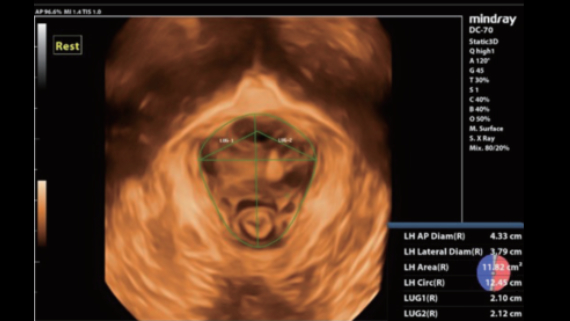

ImĂĄgenes clĂnicas